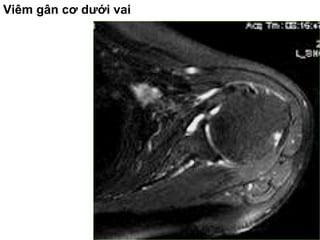

Vieâm gaân

• Gaân khoâng giaûm beà daøy, taêng tín hieäu

treân T2W beân trong gaân, möùc ñoä tín hieäu

taêng ít hôn tín hieäu dòch khôùp.

Viêm gân cơ dưới vai